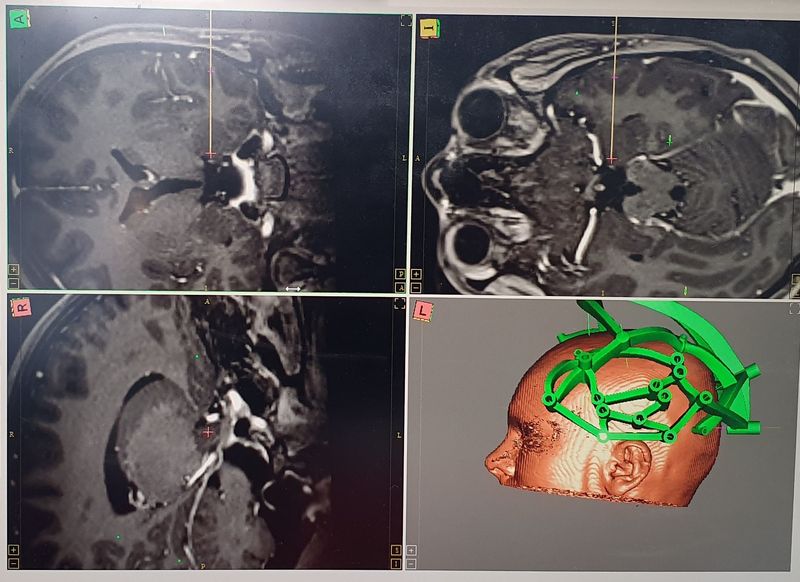

"Se face o planificare atentă folosind softuri speciale dedicate care generează un model al unei fixturi stereotactice.

Aceasta este folosită pentru a ghida electrozii conform traiectoriei planificate și este personalizată, având la bază unui set de coodonate unic pentru fiecărui pacient. Grupul nostru a contribuit la dezvoltarea modelului digital al platformei, care acum este folosit în mai multe centre din SUA și din alte țări", a declarat Andrei Barborică, fizician medical.

La intervenția chirurgicală participă medici neurologi, medici neurochirurgi și fizicieni medicali, lucrând în permanență după măsurători precise făcute în concordanță cu setul de coordonate stereotactice furnizate de software-ul de planificare chirurgicală.

"Platforma care se fixează pe capul pacientului conține ghidajele pentru traiectoriile electrozilor, iar în timpul intervenției neurochirurgul plasează fiecare electrod în ghidajele fixturii stereotactice și ajustează pozițiile prinderilor electrozilor în funcție de măsurătorile intraoperatorii", a explicat dr. Ioana Mîndruță.

"O dată ce au fost implantați electrozii intracranieni cât și electrozii de scalp, pacientul face un examen CT, se văd traiectoriile electrozilor, apoi se coregistrează, cu un software special, imaginea de la tomograf cu RMN-ul pacientului obținut anterior de intervenție, pentru a vedea exact structurile, țintele în care au

ajuns acești electrozi și traiectul de pe care înregistrează. Observăm cum sunt dispuși într-o rețea tridimensională care urmărește să țintească structurile care generează crizele pacientului și să ne aducă informații despre eventualele funcții cerebrale care nu pot fi afectate în urma ablației focarului epileptic(...) Înregistrăm semnalele intracraniene pe 128 de canale electroencefalografice, zi și noapte, timp de minimum 10 zile. În acest interval vom înregistra atât traseul de veghe, traseul de somn, cât și crizele pacientului și vom stimula creierul cu protocoale de stimulare acceptate internațional care constituie o rutină de examinare a creierului și care nu produc leziuni intracerebrale,